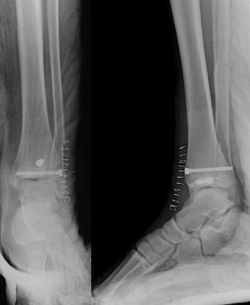

Tras conseguir una adecuada reducción de la fractura, realizamos fijación interna con 2 tornillos canulados de rosca parcial de 16 mm (un tornillo epifisario de lateral a medial y otro metafisario anteroposterior) comprobando bajo fluoroscopio la reducción de la fractura (Figura 5).

A continuación, realizamos un cierre por planos meticuloso de la cápsula articular, retináculo extensor, subcutáneo y piel, inmovilizando con un yeso suropédico. El paciente presenta una evolución inmediata favorable con dolor controlado, exploración neurovascular normal y control radiológico inmediato correcto (Figura 6).

Figura 5. Control radiológico intraoperatorio: fijación con tornillos canulados.

Figura 6. Control radiológico postoperatorio.